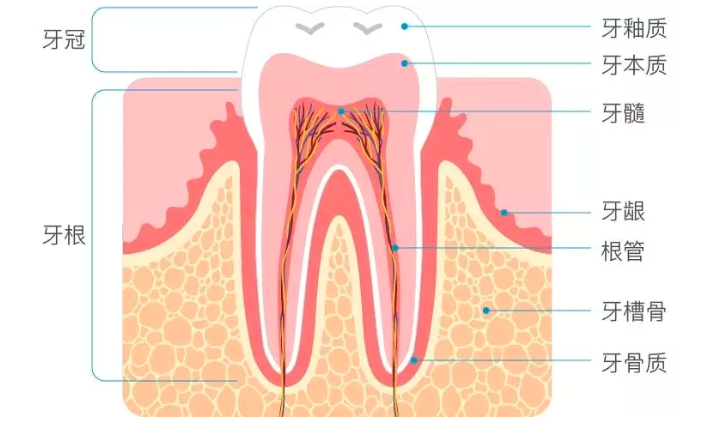

01什么是种植牙在介绍种植牙之前,老黑想请大家可以先看一下下面这张图:

没错,这就是我们牙齿的基本结构。露在牙龈外面的,也就是我们肉眼可见的白色部分,叫牙冠。而深埋牙龈和牙槽骨里面的部分,叫牙根,起到固定和支撑的作用。